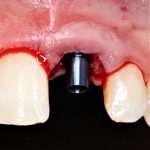

Установка имплантатов

По ряду уже упомянутых выше причин, для решения этой клинической задачи мы выбрали имплантаты Xive. Лунки для них мы уже приготовили. возможную первичную стабильность оценили. Имплантаты мы установили с усилием чуть больше 15-20 Нсм — такого крутящего момента более, чем достаточно, особенно если учесть, что временные коронки будут соединяться между собой.

Подробно о том, что такое крутящий момент и хирургический протокол можно прочитать здесь>> и тут>>, соответственно. Из-за использования специальных индивидуализируемых временных абатментов, имеющих только три положения, нам нужно позиционировать платформу имплантатов по граням. Это очень просто  — мы выводим вырез абатмента TempBase (он входит в комплект поставки) вестибулярно.

После перкуторной проверки стабильности имплантатов и точности позиционирования, мы переходим к следующему этапу — сохранению десневого контура.

Установка имплантатов занимает около двух минут.